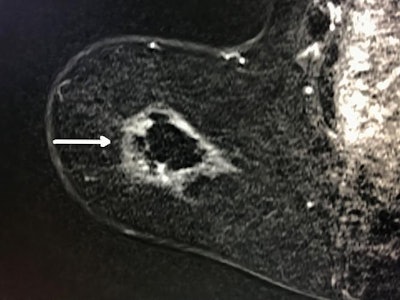

Cryoablation offers a new way to treat the disease. For the procedure, a probe is inserted into the tumor through an incision in the skin using local anesthesia. The clinician uses ultrasound to guide the probe; once it is in place, liquid nitrogen is delivered to the tumor. During an initial, eight-minute freezing cycle, the nitrogen forms an ice ball that surrounds the tumor and destroys it. After a thaw cycle, the clinician performs another eight-minute freeze cycle to make sure all of the cancer cells are eradicated. The procedure takes less than an hour, Tomkovich said.